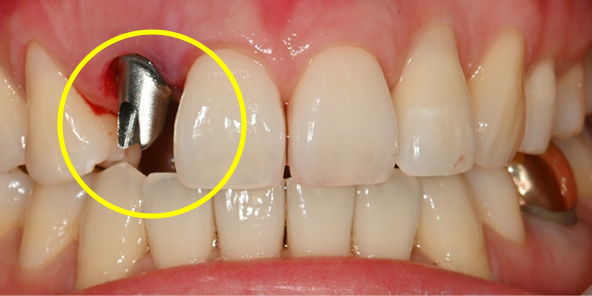

수술 당일, 계획대로 정확하게

가이드 기반 임플란트 식립

불필요한 오차를 줄이고 당일 보철까지 연결되는 핵심 단계입니다.

치료 전

발치 후 수술용 가이드를 이용해 정해진 위치에 정확하게 식립 후 미리 만들어 둔 기둥 연결

발치 후 수술용 가이드를 이용해

정해진 위치에 정확하게 식립 후

미리 만들어 둔 기둥 연결

수술 당일 보철물 즉시 완성